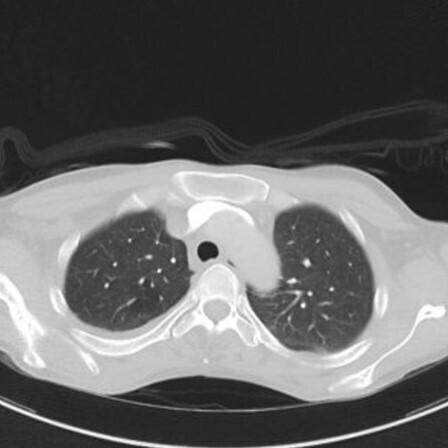

Finalement, après réinjection de produit de contraste, le scanner suivant est réalisé.

Question 15 - Quelle est votre première hypothèse diagnostique ?

Le diagnostic d’œdème aigu du poumon (OAP) se fait sur un faisceau d’arguments : la cardiomégalie avec dilatation des veines pulmonaires, les plages en verre dépoli et d’épaississement des septa interlobulaires déclives respectant les lobes supérieurs, ainsi que les épanchements pleuraux bilatéraux d’abondance modérée. L’accumulation de ces éléments rend le diagnostic d’OAP le plus probable.

Il n’y pas de défect endoluminal des artères pulmonaires permettant d’éliminer l’embolie pulmonaire. Il n’y a pas non plus de signe indirect d’embolie pulmonaire (infarctus pulmonaire).

L’hémorragie intra-alvéolaire peut aussi se manifester sous la forme de plages de verre dépoli, mais le contexte est différent, et la cardiomégalie avec dilatation des veines pulmonaires ne sont pas en faveur.

L’absence de condensation parenchymateuse et la topographie des anomalies parenchymateuses pulmonaires n’est pas en faveur d’une pneumopathie bilatérale.